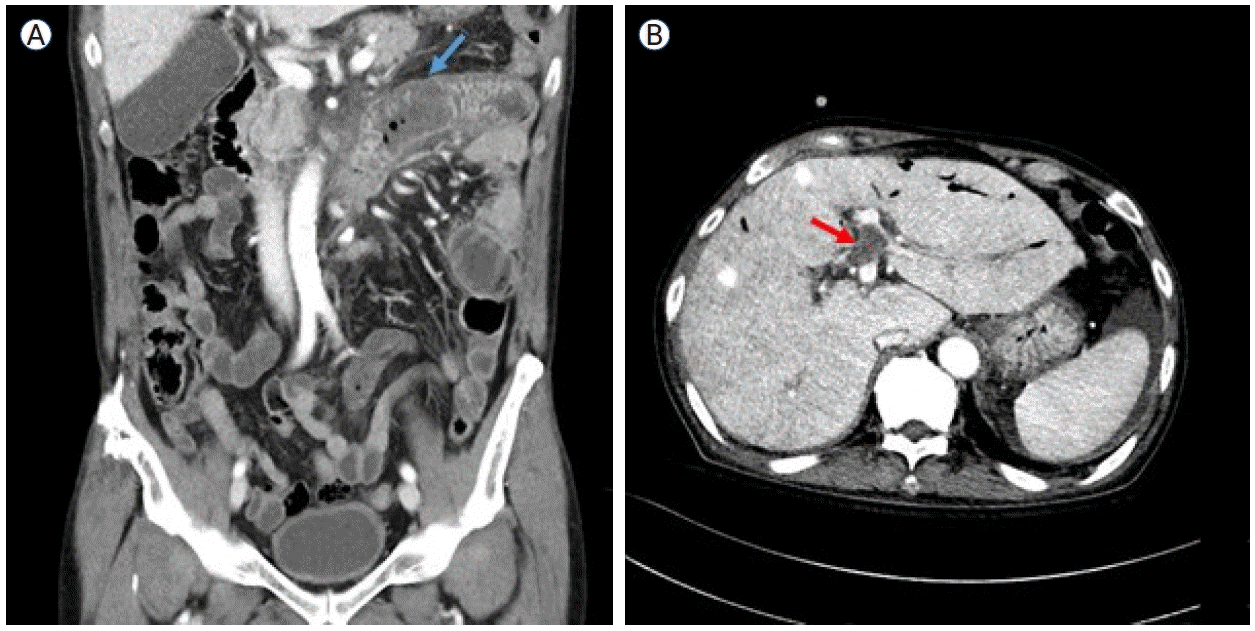

On August 19, 2024, the patient presented with abdominal pain and oral mucosal swelling. CT findings, together with dental examination results, suggested the development of ischemic enterocolitis (Fig. 2A) and necrotizing gingivitis, likely secondary to occult thrombosis. Progressive anemia (hemoglobin, 7.0 g/dL) was also noted, accompanied by gross hematuria and an elevated LDH level (787 U/L), consistent with IVH. Empirical antibiotics and intravenous steroid pulse therapy (mPD, 1 mg/kg) were initiated, resulting in symptom relief and stabilization of laboratory parameters. However, during steroid tapering, all symptoms and signs recurred, necessitating an increase in the steroid dosage. On September 19, the patient again reported abdominal pain with right upper quadrant tenderness and abdominal distension. A CT scan revealed a new non-malignant thrombus in the left portal vein (Fig. 2B) and the presence of ascites, which was further evaluated by a serum-ascites albumin gradient of 1.8 g/dL, indicating portal hypertension. On October 17, the patient developed epididymo-orchitis with a strong suspicion of ischemic infarction. Subsequently, prolonged steroid exposure led to the development of gastric and duodenal ulcers complicated by gastrointestinal bleeding, which required hemoclipping on three occasions.

Figure 2.

Computed tomography images of the patient’s abdomen. (A) Short segmental wall thickening in the proximal jejunum and the third and fourth portions of the duodenum (red arrow), suggestive of bowel ischemia secondary to occult thrombosis. (B) A newly developed thrombus in the umbilical segment of the left portal vein (blue arrow), accompanied by ascites.